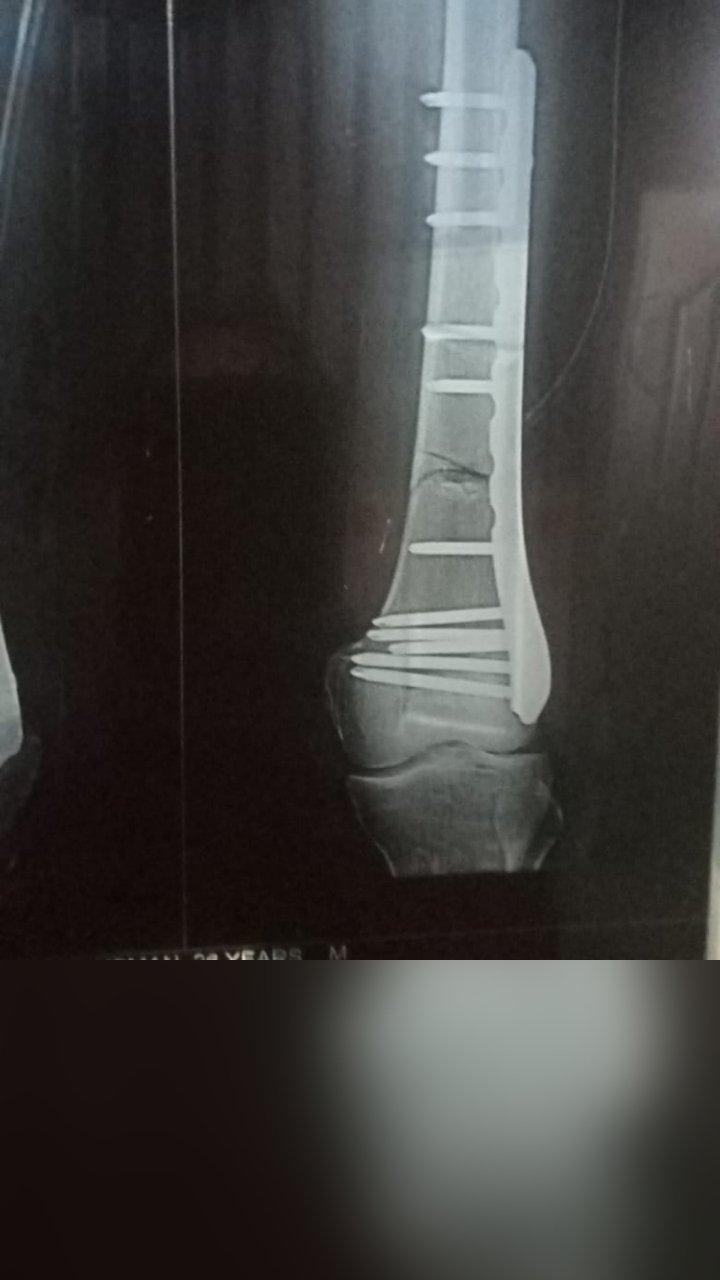

OSTEOSARCOMA DISTAL FEMUR RESECTION

FRACTURE FEMUR SURGERY

FEMUR FRACTURE SURGERY